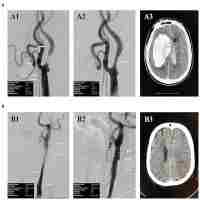

| Abstract | This study examined the association between elevated plasma homocysteine (Hcy) levels and the risk of acute cerebral infarction in patients with carotid artery lesions. A total of 78 patients were divided into two groups, the high Hcy group (n = 38; Hcy levels >15 umol/L) and the low Hcy group (n = 40; Hcy levels ≤15 umol/L). High-resolution B-mode ultrasounds were performed to assess intima media thickness (IMT), infarcts, plaques, and stenosis in the extracranial carotid artery of these patients. All patients underwent 3 T MR scanners to evaluate cerebral artery stenosis in the intracranial cerebral artery. The plasma Hcy levels did not show any statistically significant differences when comparisons were based on gender, age, blood pressure, diabetes, hyperlipidemia, and systolic and diastolic pressures. Importantly, the incidence of carotid plaque and severe stenosis of intracranial and extracranial artery were significantly higher in the high Hcy group compared to the low Hcy group. Pearson’s test indicated that plasma Hcy levels positively correlated with IMT, total number of plaques and unstable plaques. Overall, the elevated plasma Hcy levels correlated with increased frequency of carotid plaque formation, extra- and intracranial arterial stenosis, and the degree of stenosis. In conclusion, we find a significant correlation between elevated plasma Hcy levels and the increased incidence of acute cerebral infarction in patients with carotid artery lesions. |